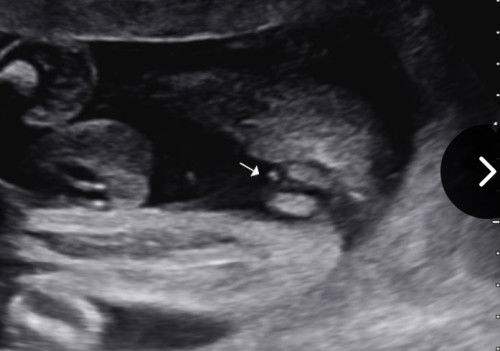

nmpk mcm bentuk burger, baby girl ni. sy dulu scan nmpk mcm ni.. keluar betul la baby girl 🩷

nmpk mcm girl..sbb dktr akn ckp klau cmni nmpk burger..burger slalu girl..klau boy nkpk pistol

mcm burger kalau sono dia kata girl